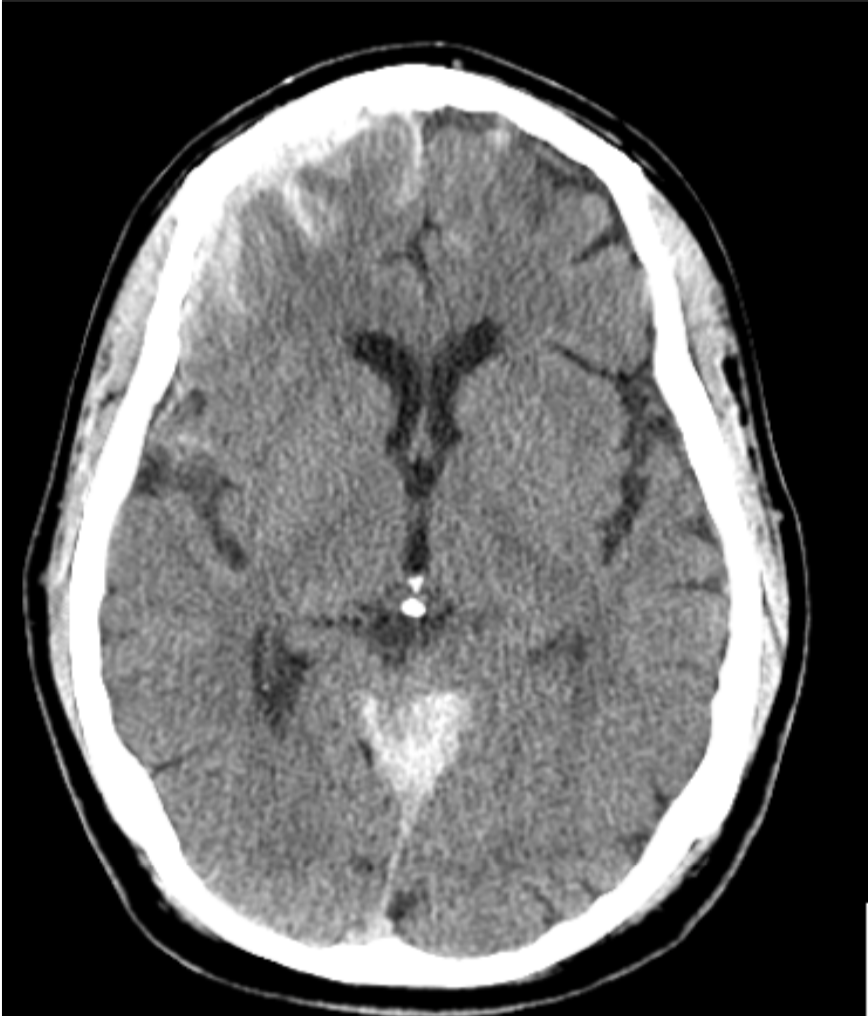

A 27 year-old man was comatose after severe head trauma.

Diffuse axonal injury